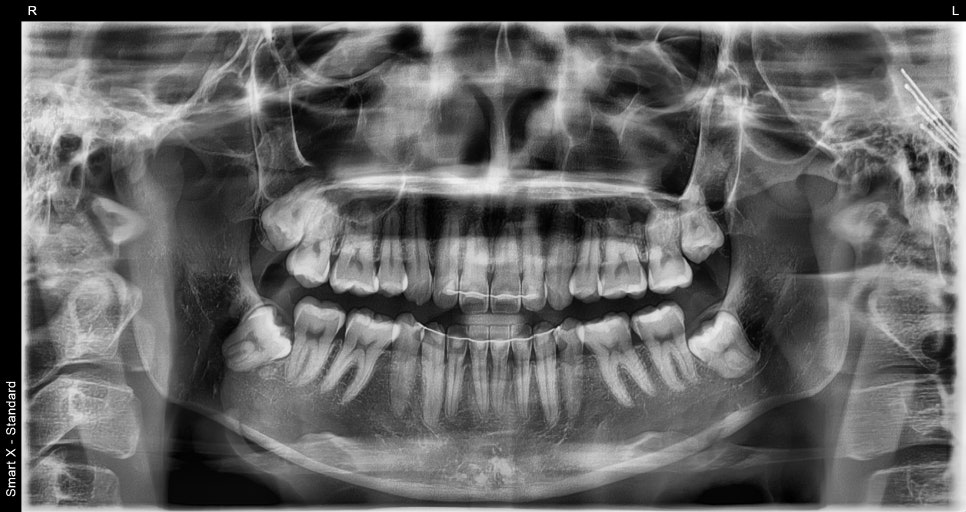

진단 및 디자인 설계

초진 상담과 디지털 분석을 통해

다음과 같은 부분을 개선하기로 했습니다:

앞니 4개(#13,12, 11, 21, 22,23)의 크기와 비율

치아 사이 미세한 틈

전체적인 치아 톤과 표면 질감

치아 삭제량은 0.1~0.2mm 이내로 제한하고,